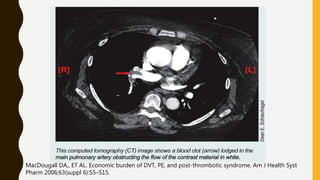

• CT pulmonary angiography (CTPA) will show filling defects

within the pulmonary vasculature with acute pulmonary emboli.

• When the artery is viewed in its axial plane the central filling

defect from the thrombus is surrounded by a thin rim of

contrast, which has been called the Polo Mint sign.

RV

MacDougall DA,, ET AL. Economic burden of DVT, PE, and post-thrombotic syndrome. Am J Health Syst

Pharm 2006;63(suppl 6):S5–S15.